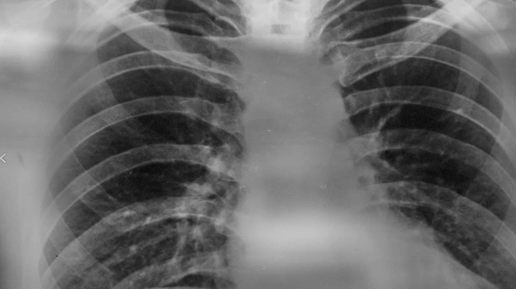

Бронхит – это воспаление слизистой оболочки бронхов, крупных дыхательных путей, которые доставляют воздух в легкие и из них. Это распространенное заболевание, которое может поражать как взрослых, так и детей. Хотя бронхит часто начинается как обычная простуда, важно распознать его первые симптомы, чтобы своевременно начать лечение и предотвратить развитие осложнений, таких как пневмония или хроническая обструктивная болезнь легких (ХОБЛ). В этой статье мы подробно рассмотрим ранние признаки бронхита,...

Симптомы и лечение хронического бронхита курильщика

Каждый человек знает, что курение, сильный кашель и одышка связанны неразрывно. Чаще всего такая проблема сигнализирует о наличии какой-либо патологии в дыхательных путях. Именно поэтому так важно знать про симптомы и лечение бронхита курильщика. Необходимо своевременно диагностировать заболевание, иначе оно приобретет хроническую форму и спровоцирует возникновение ряда других серьезных болезней. Причины болезни Курение - это пагубная привычка. Об этом все знают. При длительном курении развиваются плохо обратимые изменения в дыхательной системе...